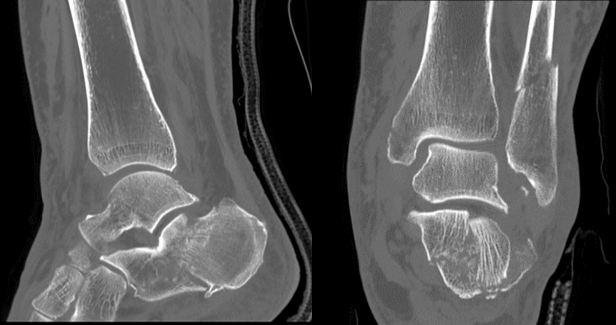

・ハイレゾリューションモードで微細な骨折描出

ハイレゾリューションモードが有効であった足関節の症例を提示します。

高分解能モードを使用することにより、骨梁まではっきりと画像化することができます。

本症例は複数の骨が骨折をしている症例ですが、どの骨においても細かな骨折線や骨片まで描出することができています。